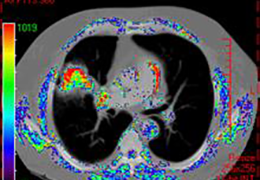

View X-Ray CT & MRI Scans Fast and Easily

Designed for surgeons, Pro Surgical 3D makes it easy to view patient scans quickly. Pro Surgical 3D facilitates the optimal 3D treatment and assessment workflows based on X-ray CT and MRI scans – and best of all, it’s FREE!

Designed mainly for CT and MR DICOM modalities.

Performs 3D reconstruction and volume rendering.

Multi-planar slicing.